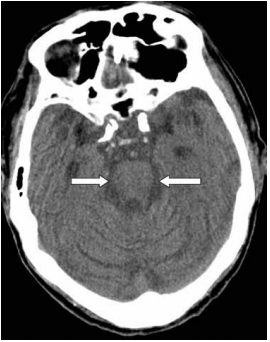

53 附圖中箭號所指的實質構造最可能為何?

(A) medulla oblongata (B) pons (C) cerebral peduncle (D) cerebellar peduncle